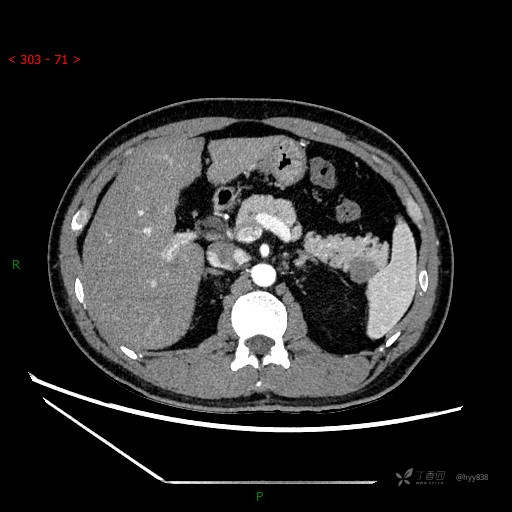

胰腺CT平扫

增强动脉期